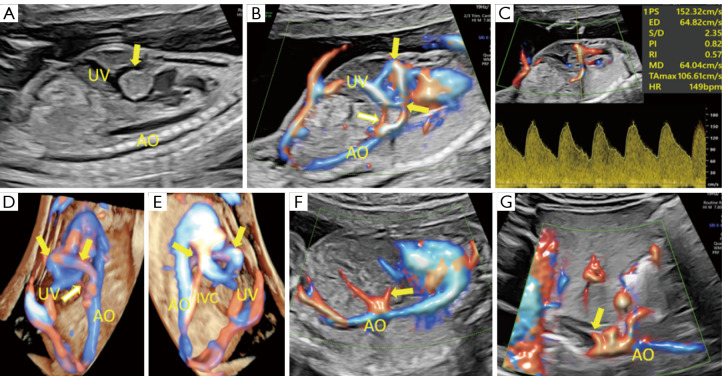

Prenatal diagnosis of abdominal aorta-umbilical vein fistula using high-definition flow render mode and spatiotemporal image correlation.

应用高清血流渲染模式和时空图像相关技术产前诊断腹主动脉-脐静脉瘘。